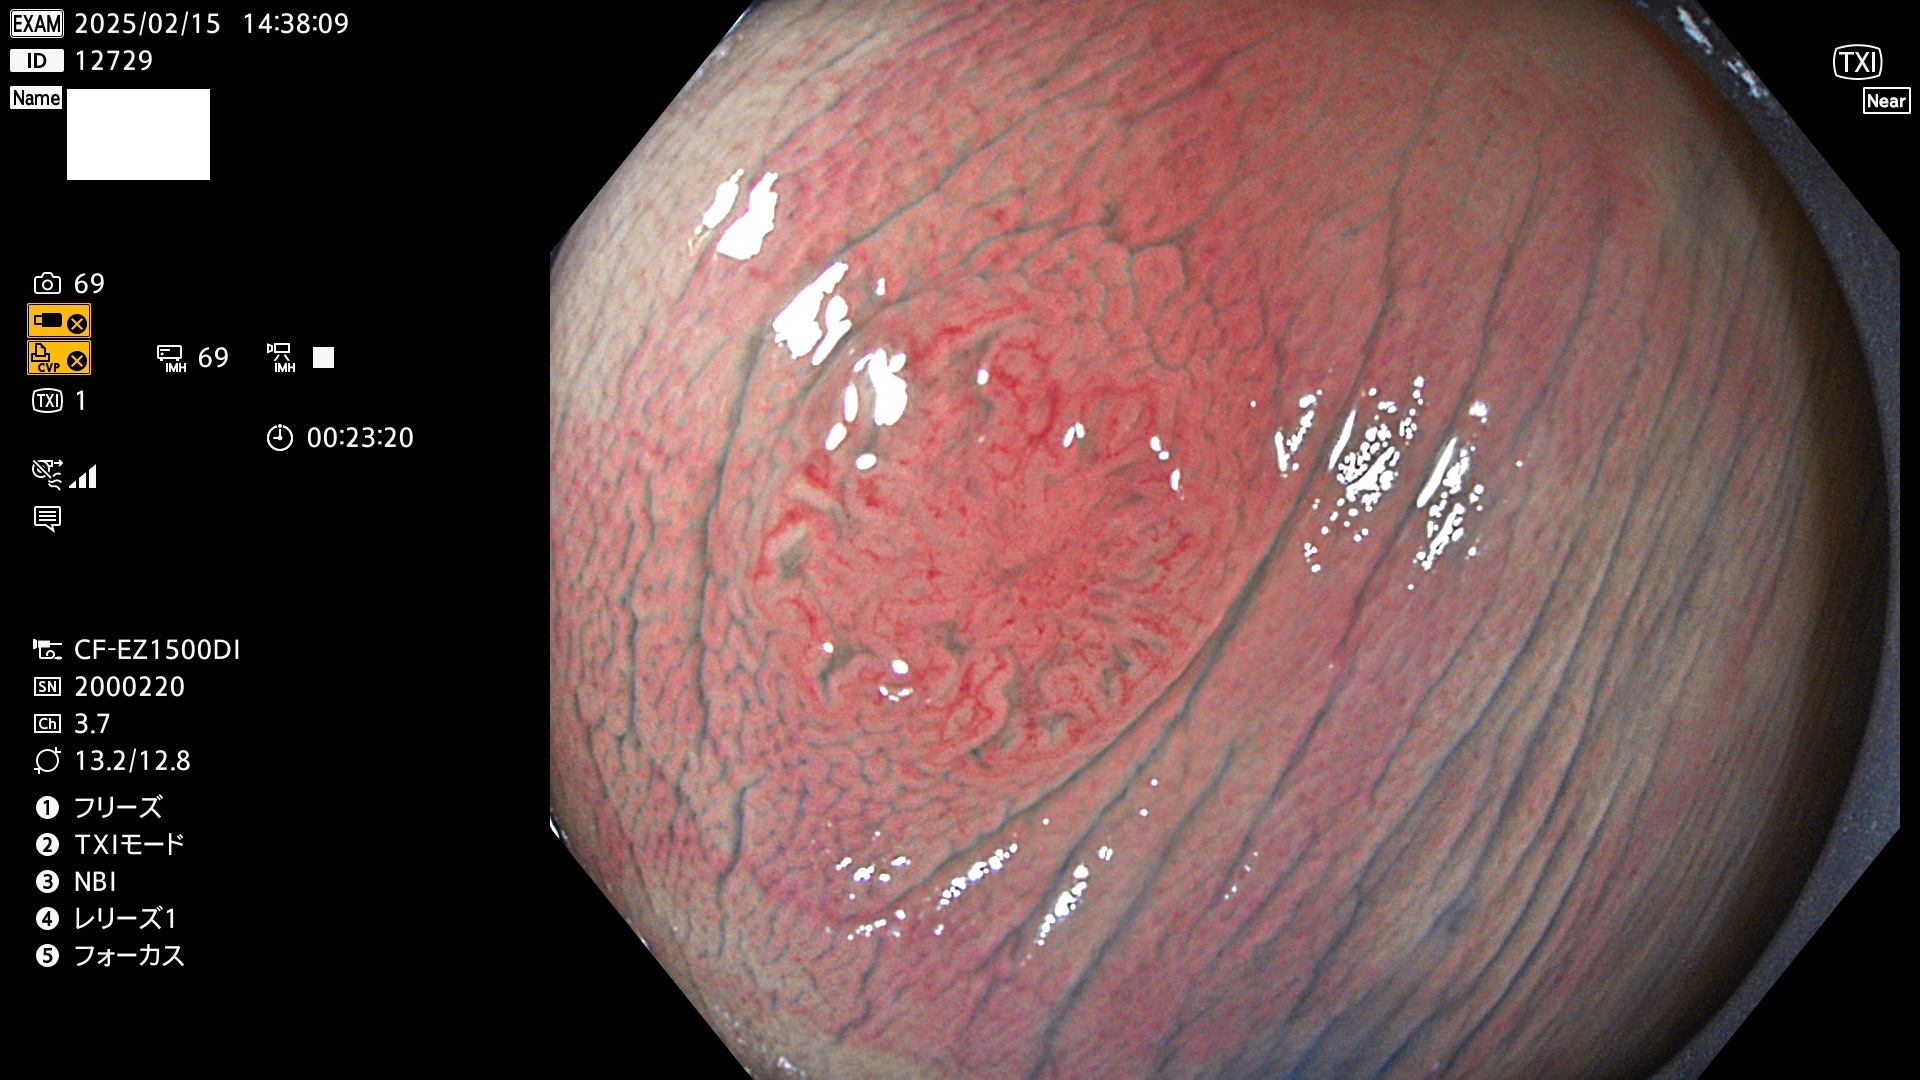

今週のUb、Uc型腺腫

完全に平坦な物をUb、陥凹している物をUcと呼びます。最も発見が難しく危険な病変です。

毎週の検査(木・金・土・日)に発見されたUb、Uc型・腺腫を、その週の日曜の夜にUPし1週間、提示します。

抽出の対象期間 2025年2月13日〜2月16日の4日間(48件の検査)8個 (8/48=16%)